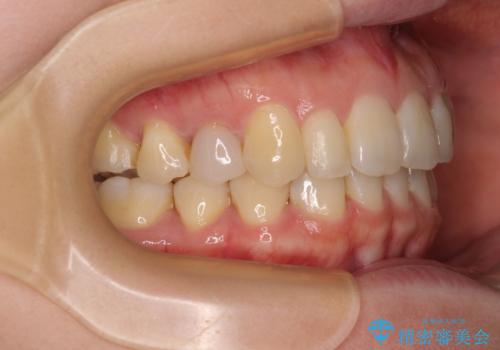

先天欠損のある歯列 インビザライン矯正

- 上顎前歯の突出感を気にして来院された患者様です。

下顎前歯2本が先天欠損しており、上顎歯列に対して、下顎歯列がアンバランスに小さい状況でした。

左右上顎側切歯2本が矮小歯であるため、上顎の抜歯ではなく、IPR(歯と歯の間を削る)と歯列全体の後方移動によってバランスを整えることとしました。

目立ちにくい装置を希望されたため、インビザラインにて治療を行うこととしました。